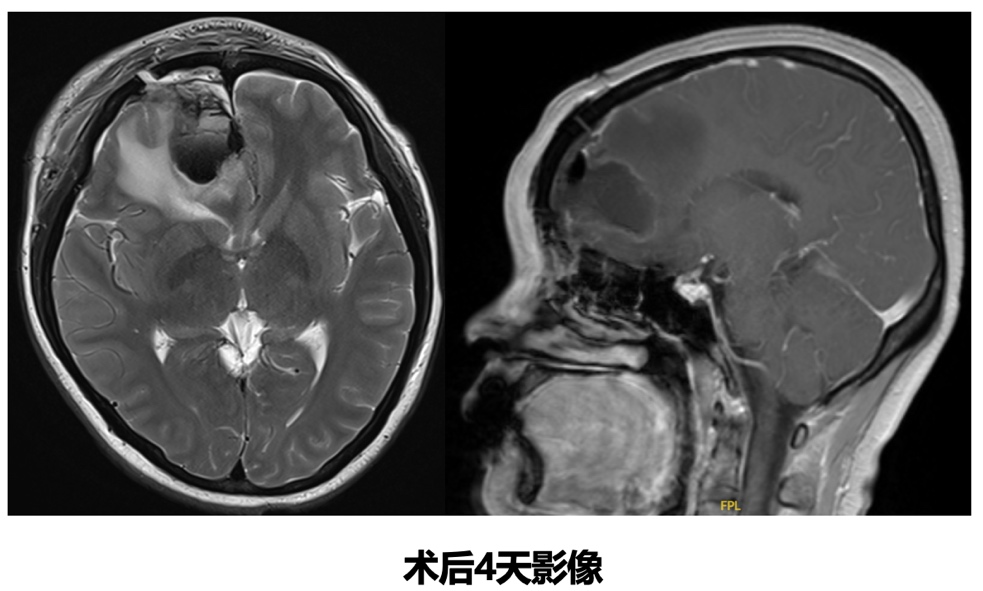

脑转移瘤局部手术治疗

神经外科会诊考虑患者为孤立性脑转移瘤,且存在明显占位效应,符合局部手术治疗条件,于2025-5-20行“右侧额叶占位显微切除+人工硬脑膜修补+颅骨骨瓣修补术”。

病理

(右侧额叶病灶)符合乳腺癌转移。IHC:GATA-3(+)、TRPS1(+)、ER约20%弱-中等(+)、PR<1%(+)、Her-2(3+)、Ki67约25%(+)、CAM5.2(+)、CK7(-)、CK5/6(-)。